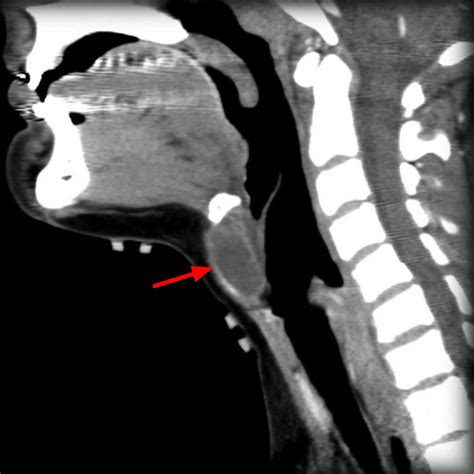

The diagnosis of a Cyst Thyroglossal Duct typically involves a combination of physical examination and imaging studies. The healthcare provider will perform a thorough physical examination to assess the size, location, and characteristics of the cyst. Imaging studies, such as ultrasound, computed tomography (CT) scan, or magnetic resonance imaging (MRI), may be ordered to confirm the diagnosis and rule out other potential causes of the neck mass.